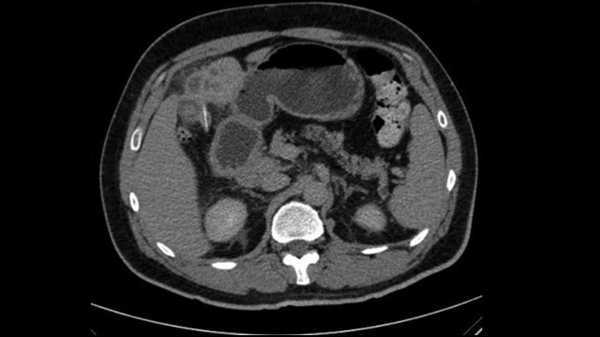

Що сталося далі: З часом пацієнтка більше не могла терпіти тривалі сеанси діалізу, тому вона починала та закінчувала кожен сеанс з вагою, що перевищувала її цільову, через накопичення рідини. Вона також повідомляла про періодичні запори.

Після одного сеансу діалізу медсестра, яка чистила крісло, на якому сиділа жінка, зазначила, що воно було «досить легким». Під час огляду вона помітила, що на кріслі бракувало великих шматків піни, зокрема поліуретану низької щільності.

Їй також призначили проносне, щоб допомогти їй вивести з'їдену піну без будь-яких ускладнень. На момент публікації звіту про випадок у 2010 році вона продовжувала проходити діаліз тричі на тиждень.